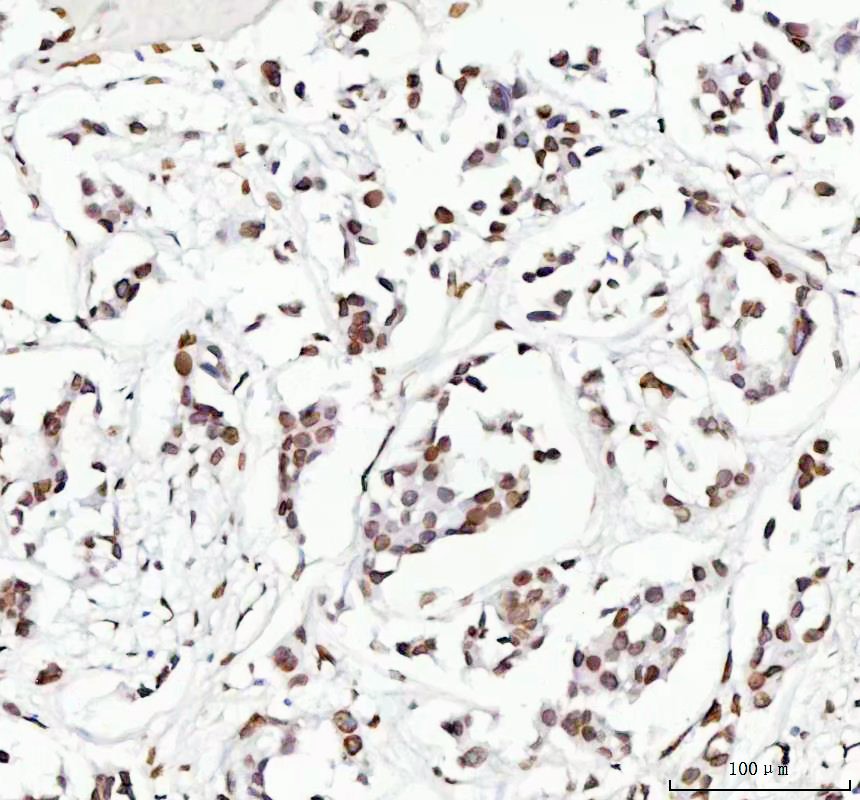

IHC analysis of Lamin B2/LMNB2 using anti-Lamin B2/LMNB2 antibody (BM5380) .

Lamin B2/LMNB2 was detected in a paraffin-embedded section of human lung cancer tissue. The tissue section was incubated with rabbit anti-Lamin B2/LMNB2 Antibody (BM5380) at a dilution of 1:200 and developed using HRP Conjugated Rabbit IgG Super Vision Assay Kit (Catalog # SV0002) with DAB (Catalog # AR1027) as the chromogen.